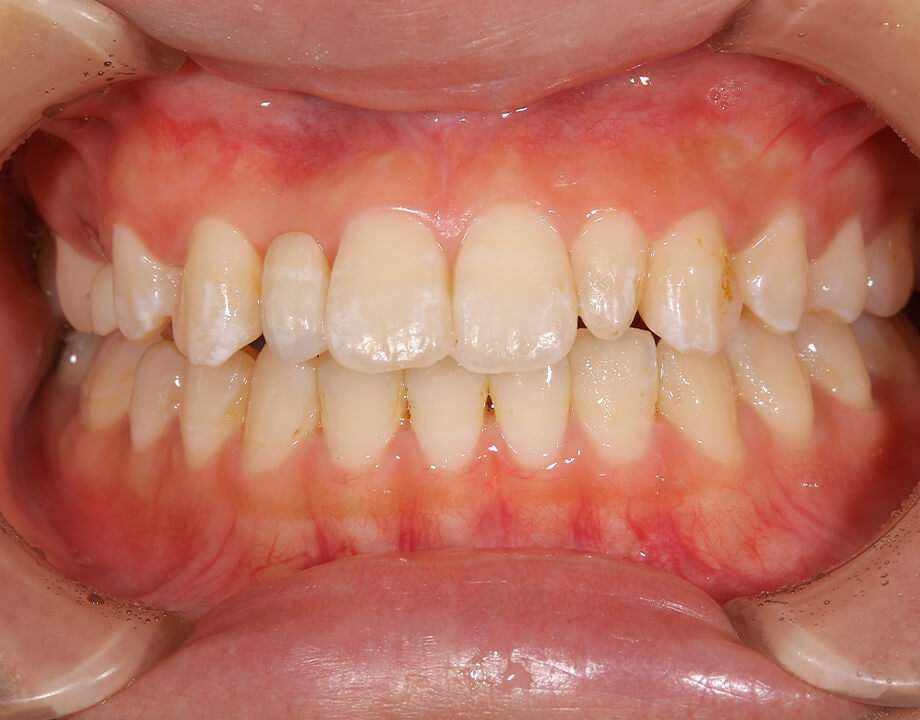

Case 03インプラント

モノリシックジルコニア